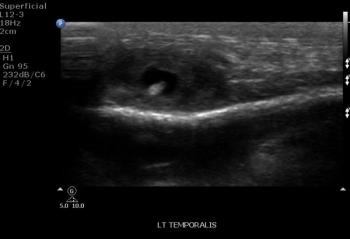

A 13-year-old female presents with painful swelling in the left temporal region.